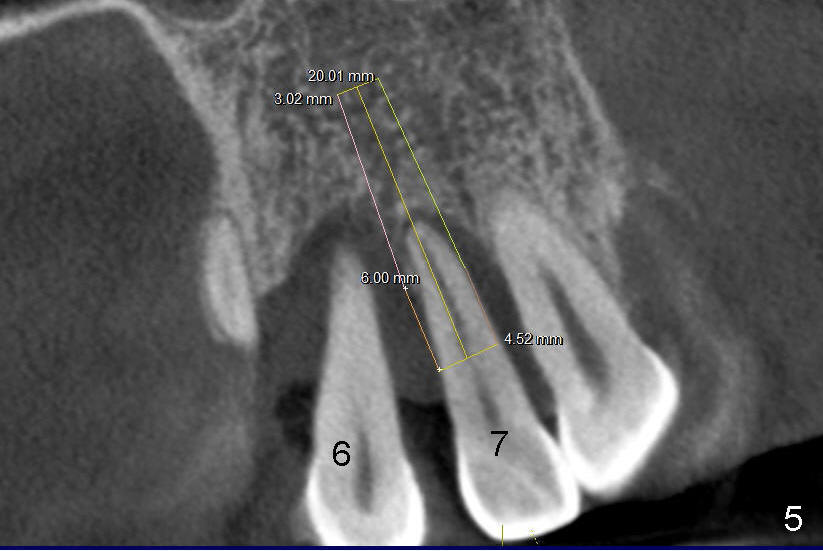

12. Bicon reamers, save bone, later mix with synthetic bone (Osteogen), reamers until 3.0 mm for #7, 3.5 for #6, tap 4.5x20 for 6, then 5x20, possibly 6x20

14. Place implants as palatally as possible. Use Tatum tapered drills if orientation changes unfavorably